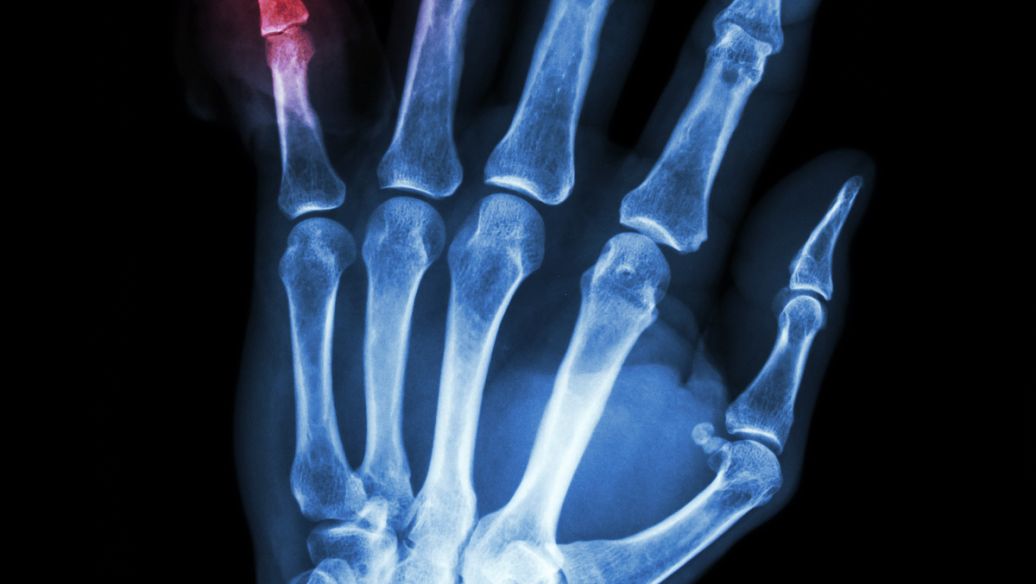

痛风性关节炎: 这是最常见的并发症,是由于尿酸结晶长期沉积在关节中,引起的慢性关节炎。它会导致关节变形、僵硬、功能障碍,甚至残疾。常常影响手指、脚趾、膝盖、肘部等关节,严重影响日常生活和工作。